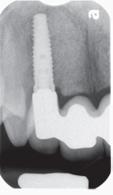

60 Top Dentists 2025

The annual Top Dentist list showcases excellence in dental care. See which New Hampshire dentists were voted by their peers as the most trustworthy.